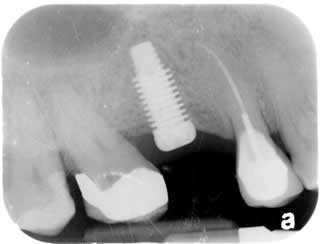

Implant Crown:

The one 3rd from the left is the implant crown. The good thing about this implant crown is that there will be no recurrent decay underneath of implant crown as compared to the regular tooth crown.